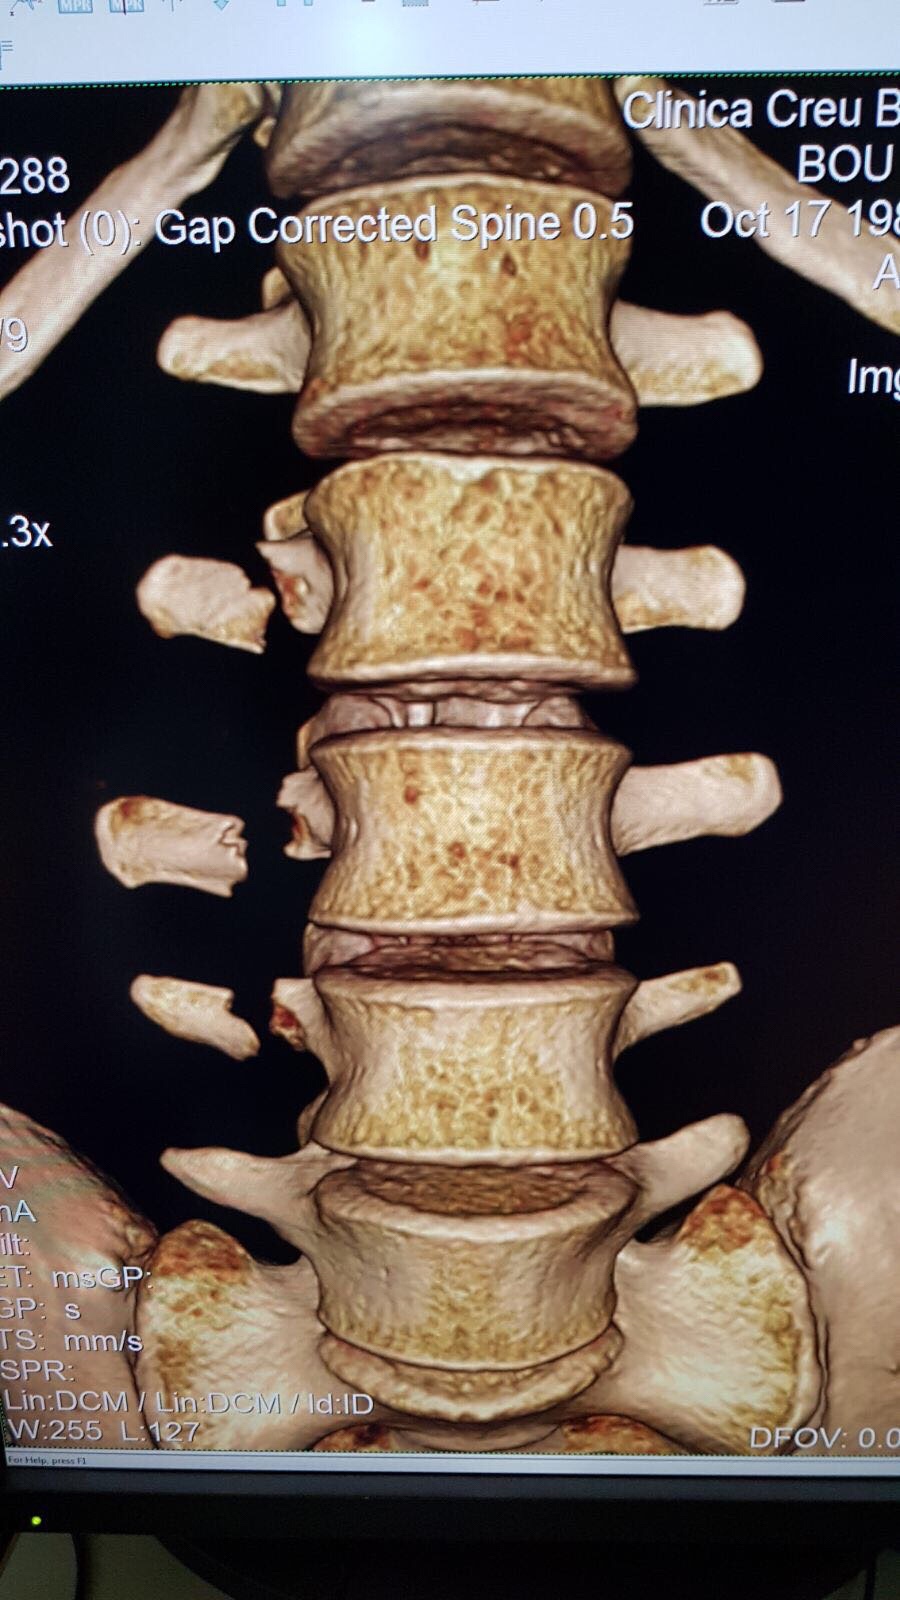

I dag, måndag, efter medicinska tester som utförs av lagets läkare Joaquim Terricabras på Consell Català de L’Esport och Creu Blanca Clinic i Barcelona, har det bekräftats att Toni Bou har drabbats av en fraktur på högra apophysis tvärs ländkotorna L2 -L3-L4.

Dr. Terricabras har rekommenderat vila från all idrottsverksamhet för Bou, som säger att utvecklingen av skadan kommer att diktera när Bou kan återvända till tävlandet, även om det är osannolikt någon gång under de kommande tre veckorna.